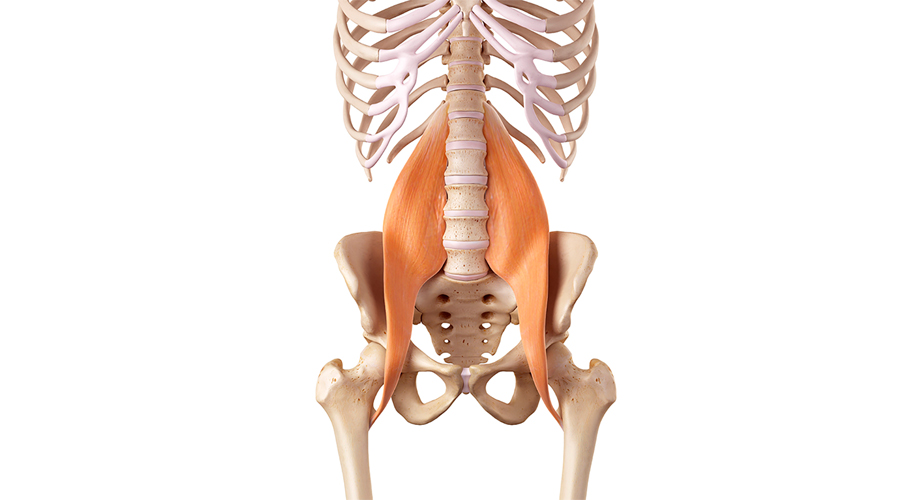

7. 코어 강화 운동

코어 강화 운동은 코어, 등 및 골반 근육을 포함하여 척추를 지탱하는 근육을 강화하는 것을 목표로 합니다. 코어는 몸통을 지탱하는 근육으로, 허리디스크를 보호하는 역할을 합니다.

코어 강화 운동을 하면 허리 근육이 강해져서 허리디스크를 보호하고 통증을 줄일 수 있습니다. 대표적인 운동법의 예시로는 플랭크가 있습니다.